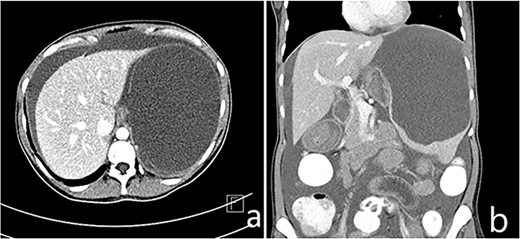

A 33-year-old female patient presented to the Emergency Department with a complaint of abdominal pain for the past 4 months. The pain was mainly localized to the left upper quadrant and epigastric area and was associated with nausea, post-prandial vomiting and early satiety. On examination, a palpable mass was discovered in the left upper quadrant extending to the peri-umbilical area. There was no tenderness or guarding. There was no history of weight loss or other constitutional symptoms. Laboratory investigations were unremarkable. Other systemic examinations were also unremarkable. There was no significant family history. The patient underwent an ultrasound of the abdomen that showed a splenic hypoechoic cystic lesion with hypoechoic and hyperechoic septa. Abdominal CT imaging revealed an enlarged spleen (about 19 cm) with a large splenic cyst measuring about 15.7 × 12 × 10 cm3 with mass effect on the stomach, displacing it to the right side with marked intraperitoneal free fluid seen (Fig. 1). Both splenic cyst content and ascites show the same criteria on ultrasound, and the same HU density. There were no other findings detected in the abdomen. The initial differential diagnosis based on imaging included splenic cyst and neoplastic lesion. After a thorough discussion with the patient, it was decided to go forward with total splenectomy for definitive diagnosis and symptom relief. The patient was administered the required vaccines 14 days prior to the surgery as per guidelines. The patient underwent laparotomy via a midline vertical incision. The outer surface of the spleen was irregular and brownish-grey colored with multiple nodular formations. Gross sections showed cystic cavities of different sizes. The largest one measured was 11 × 5 × 9 cm3 with some wall calcifications. The rest of the splenic parenchyma had no remarkable changes. Histopathological examination revealed multiple cystic spaces, lined by flattened endothelial cells. The lumens were filled with proteinaceous material (Fig. 2). Immunohistochemistry was not done at our center due to unavailability. There were no intra-operative complications and post-operative recovery was satisfactory. She was discharged on the fourth post-operative day. There was mild thrombocytosis (590 × 109/L) post-operatively, which returned to normal levels subsequently in the following weeks. The patient was followed up for the next 3 months with satisfactory recovery.

(a and b) Enlarged spleen (about 19 cm) with a large splenic cyst measuring about 15.7 × 12 × 10 cm3 with mass effect on the stomach displacing it to the right side with marked intraperitoneal free fluid seen (ascites).